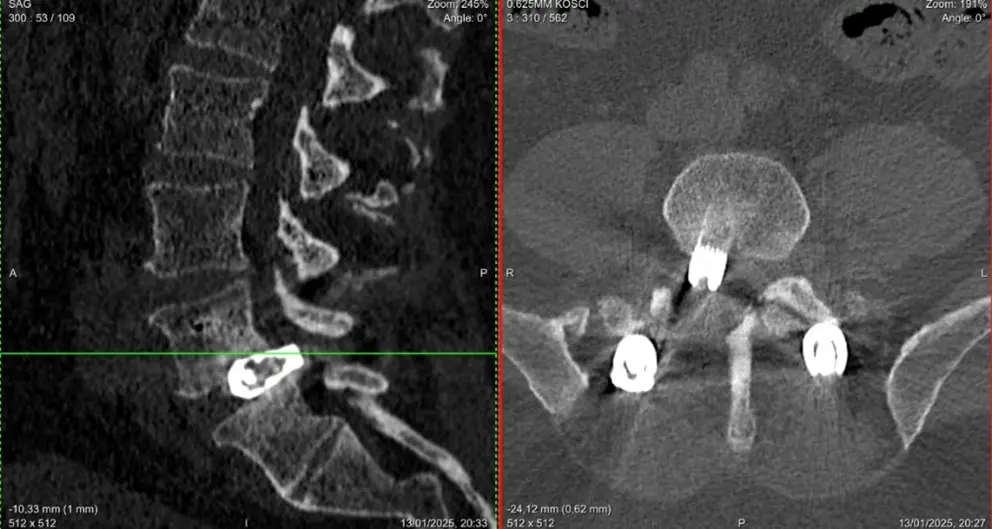

Przy wykonaniu pierwotnej stabilizacji u pacjenta wystąpiły problemy z implantem i nie dało się go stabilnie ustawić. Po kilku miesiącach implant „powędrował” do tyłu, co widać na zdjęciu. Przemieszczenie implantu spowodowało kolizję z korzeniem. Pacjent początkowo czuł się dobrze, jednak powróciły dolegliwości bólowe nie tylko kręgosłupa, ale także kończyn dolnych.

1. Stabilizacja jednopoziomowa w odcinku lędźwiowym

2. Usunięcie implantu międzytrzonowego i stabilizacja kręgosłupa lędźwiowego ALIF z dostępu przedniego (nowy implant)

3. Endoskopowe usunięcie przepukliny dysku z odbarczeniem stenozy kanału kręgowego

Operację przeprowadzili neurochirurdzy Jurij Kseniuk oraz Maciej Bujko.